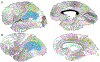

The purpose of this review is to describe the functional anatomy of the precuneal cortex and outline some semiological features of precuneal seizures. The precuneal cortex is a structure that occupies the posterior medial portion of the parietal lobe, and it has broad cortical and subcortical connections. Neuroanatomical tracing, functional imaging, as well as electrical stimulation studies of humans and other primates have elucidated many complex integrative functions of the precuneus including visuo-spatial imagery, sensorimotor functions, and consciousness. Based on the understanding of its functions and connectivity, descriptions of potential seizure semiologies are hypothesized and compared to what is available in the literature. The latter is mostly in the form of case reports or case series. Seizures may involve simple or complex motor or sensory manifestations including abnormal eye movements, visual hallucinations, sensation of motion, or medial temporal-like seizures.